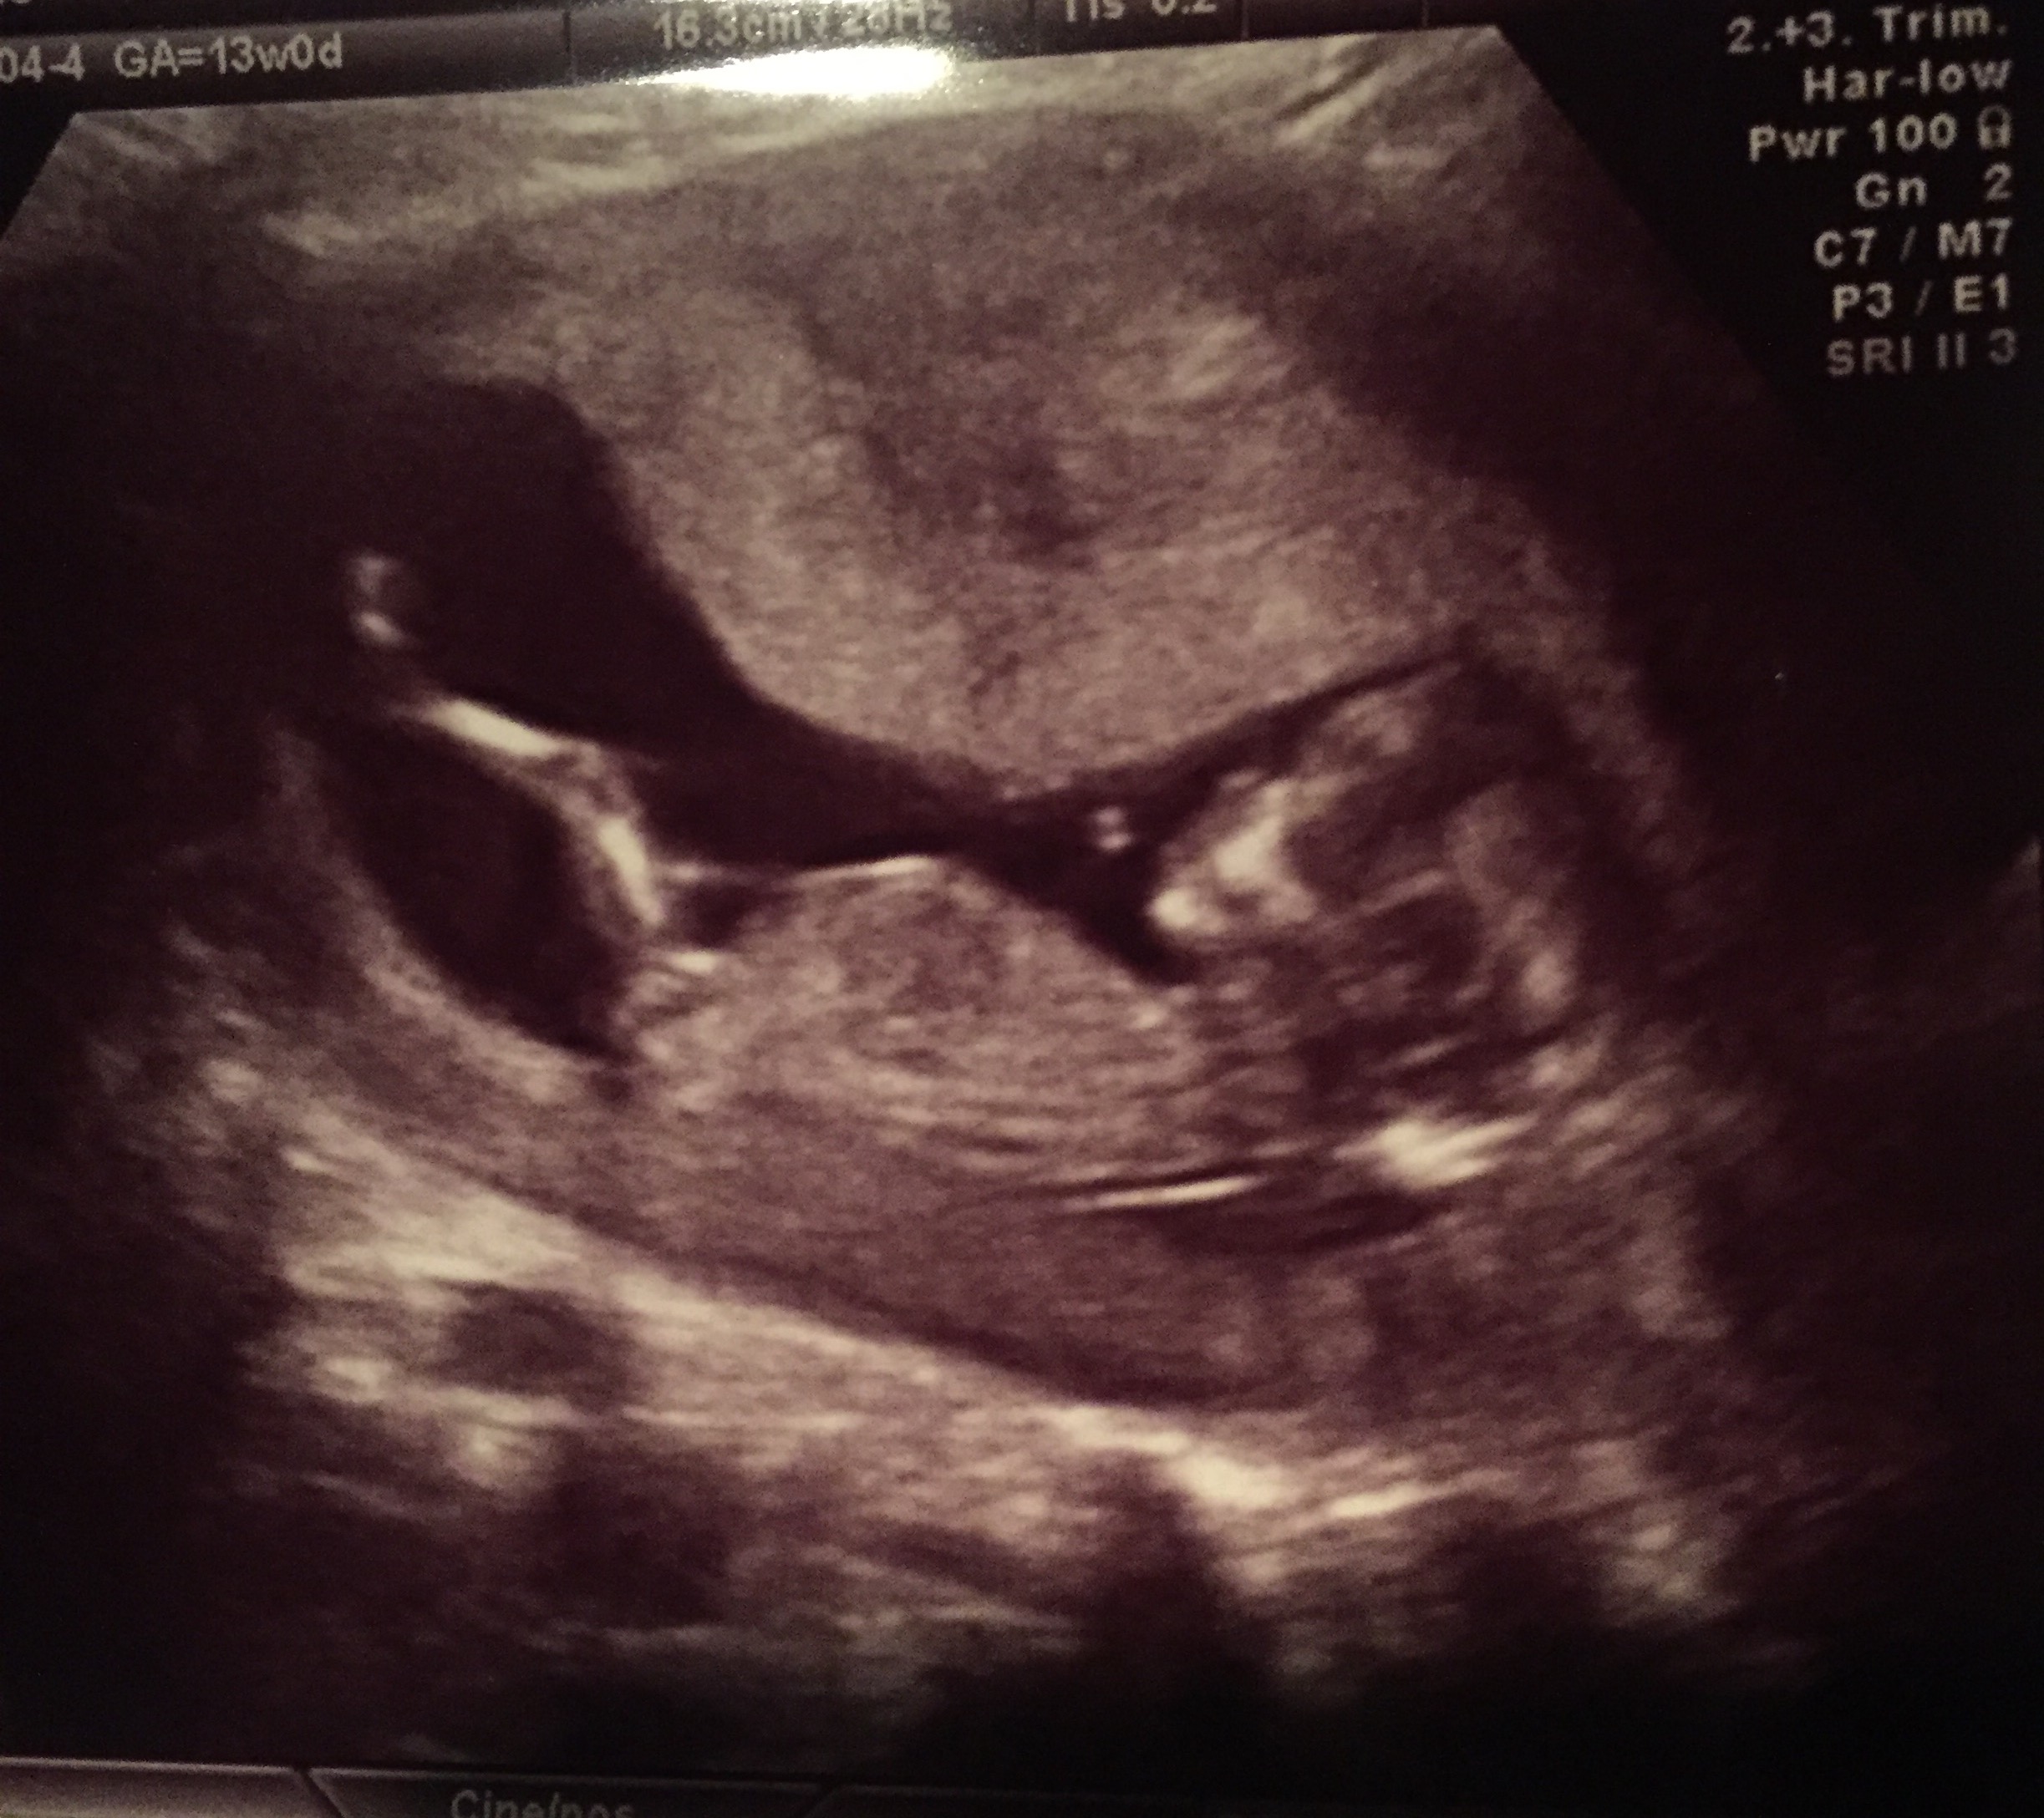

@CopperLane thanks! The tech actually got super frustrated Bc he wouldn't wake up and move so she could measure his neck. She kept pounding on my stomach with the wand and he wouldn't budge. Finally he turned-but the wrong way and just mooned the tech. She let out a big huff of frustration and I said: "Is he pissing you off? Definitely my kid."

Our NT scan today revealed what the tech said was the most stubborn fetus he's tried to measure in some time. Got a picture with the tips of all 5 fingers up by their face. 12w4d, heart rate of 153 (I think).